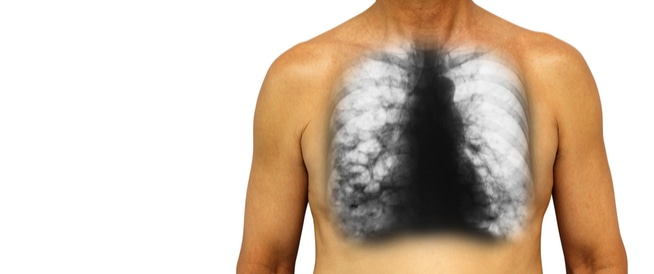

التهاب الشعب الهوائية هو التهاب في البطانة المخاطية الداخلية للقصبات الهوائية في الرئتين، ويُعد السعال المزعج أحد أكثر أعراض التهاب الشعب الهوائية شيوعًا، حيث يبدأ السعال عادةً جافًا، ثم يُنتج بلغمًا في النهاية، مما يُصعّب التنفس، وبعض حالات التهاب الشعب الهوائية تزول من تلقاء نفسها.

يُسبب التهاب الشعب الهوائية التهابًا في الشعب الهوائية في الرئتين، وهناك نوعان مُميزان من التهاب الشعب الهوائية: حاد قصير الأمد، ومزمن طويل الأمد.